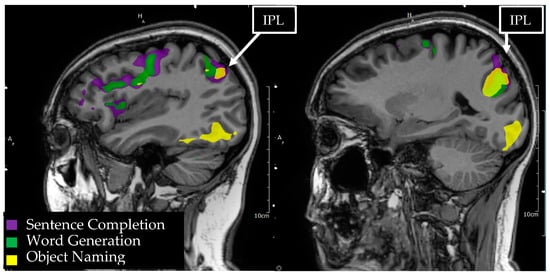

3.10. Inferior Parietal Lobule/Geschwind’s Area